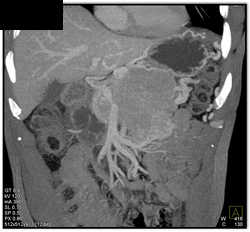

Carcinoma of the Pancreas